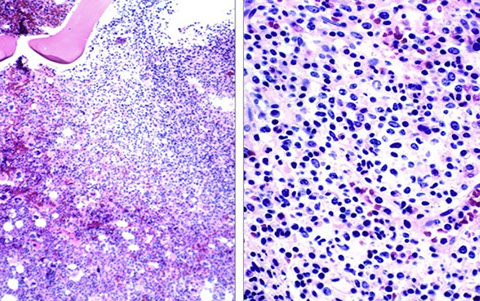

CLL pseudofollicle (proliferation center). Little lymphocytes with small cytoplasm on the left. On the right, paraimmunoblasts are larger, with a little more cytoplasm, with prolymphocytes (black arrow)showing dispersed chromatin, and the red arrow to paraimmunoblasts with prominent central nucleolus (called "paraimmunoblasts" because typically smaller than B-type immunoblasts).